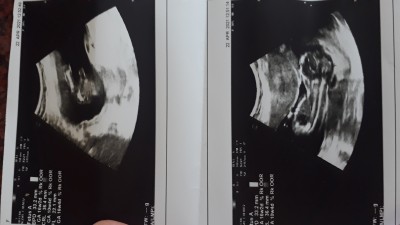

Lutfen nub teorisinden anlayanlar bi baksin ya

bugün doktor erkeğe benzetti sizce nedir 16 haflik

Söylemesi gerekti artık 16 haftalık mış

Evet bende sordum 3 kez devlet olduğu içün sadece erkeğe benziyor dedi

Bence de erkek

Bencede erkek canim zaten nüb teorisi 10 haftalarda falan tutuyor 16. haftada olmaz bacak arasında net çıkmış zaten

Hmm doğrudur canım devlet e gittim icin pek ilgilenmeyip benziyor kalk dedi o yüzden sormak istedim teşekkür ederim